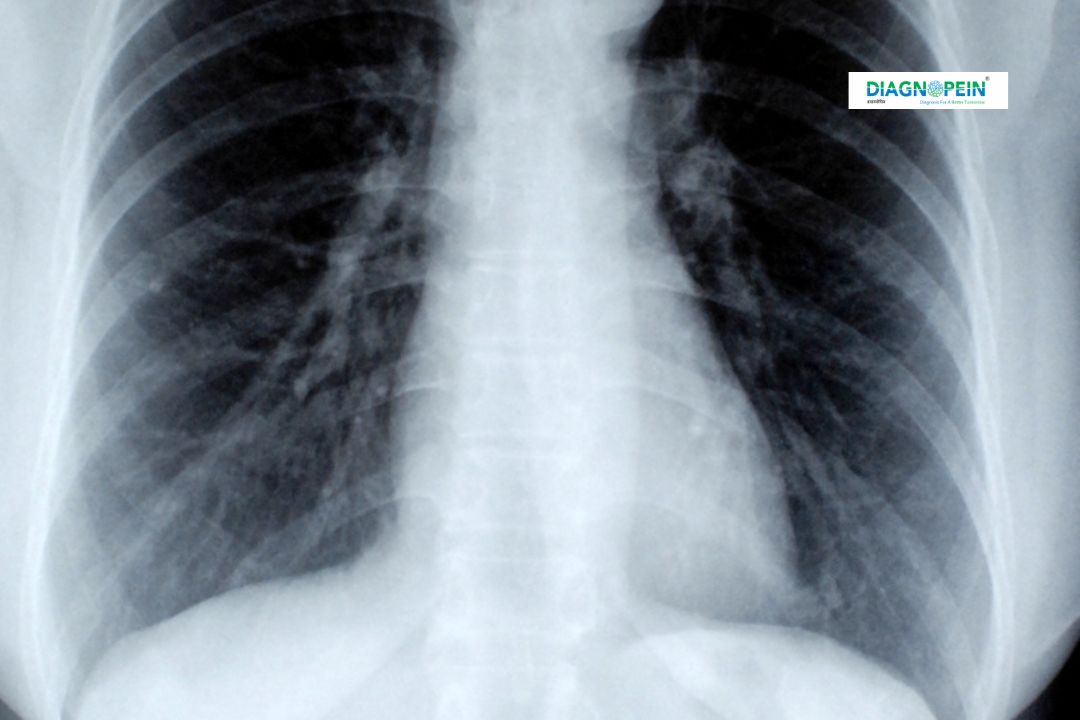

X-Ray AP (Anteroposterior) and LAT (Lateral) RT & LT Arthrography are advanced imaging techniques used to examine the joints, bones, and soft tissues of the right and left sides of the body. This diagnostic test helps radiologists visualize joint structures in greater detail, making it easier to identify abnormalities such as ligament tears, fractures, or cartilage issues.

X-Ray AP/LAT RT & LT Arthrography is an enhanced X-ray procedure where a contrast medium (arthrographic dye) is injected into the joint before taking the X-rays. This allows the radiologist to examine the inner structure of the joint more clearly than with a regular X-ray.